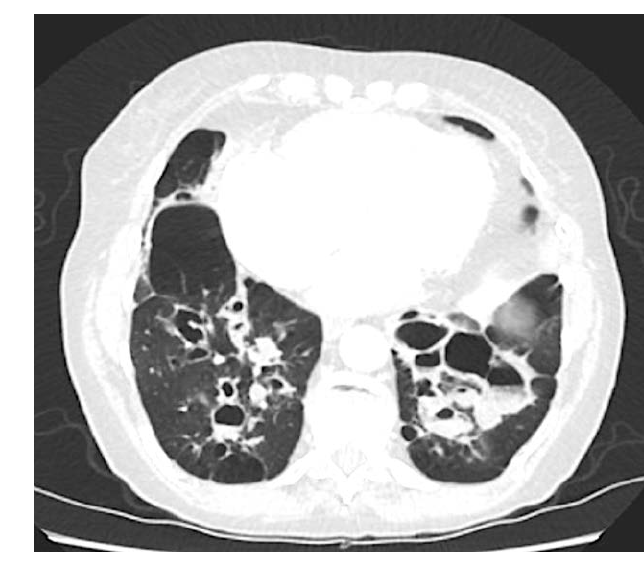

What is this? What feature do we see?

cystic bronchiectasis. ballooning bronchi

What is this?

cylindrical bronchiectasis